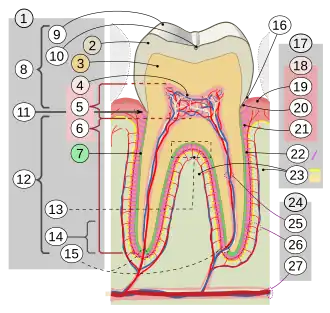

Цемент (лат. cementum) — специфическая костная ткань, покрывающая корень и шейку зуба человека, а также зубов других млекопитающих. Служит для плотного закрепления зуба в костной альвеоле. Цемент состоит на 68—70 % из неорганического компонента и 30—32 % из органических веществ.

Цемент подразделяется на бесклеточный (первичный) и клеточный (вторичный).

Первичный цемент прилежит к дентину и прикрывает боковые поверхности корня.

Вторичный цемент покрывает верхушечную треть корня и область бифуркации многокорневых зубов.